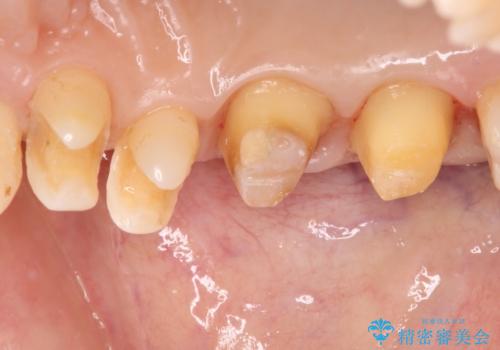

- 奥歯の銀歯をセラミックの白い歯にして、しみる症状も改善したいとのことで来院された患者様です。

知覚過敏の症状が強い歯と、銀歯の範囲や銀歯の下のむし歯が大きい歯は、インレー修復では対応が難しいためオールセラミッククラウンで、インレー修復で対応が可能な歯ではセラミックインレーにて修復することとしました。